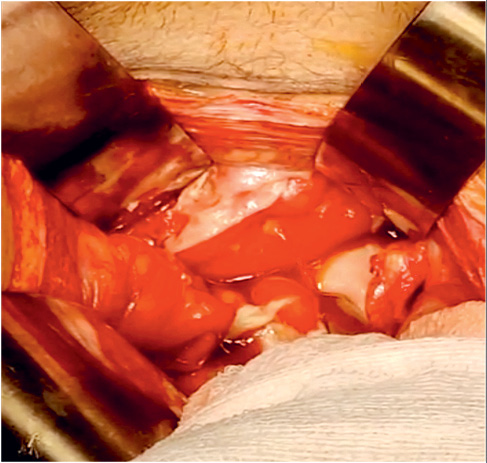

Following initial stabilization, he was taken up for emergency exploratory laparotomy. A midline incision was used to enter the abdominal cavity. Intraoperatively, there was gross free fluid inside the abdominal cavity. The consistency was thick and fibrinous. There were multiple intraop purulent fluid collections. There was similar fluid found in the pelvic cavity and also in the right subhepatic space. Bowel loops were grossly oedematous and distended. There were multiple flakes of fibrin deposits over many parts of the bowel loops. The omentum was pulled towards the urinary bladder area with dense adhesions. The pulled omentum was causing a band like constriction on the mid transverse colon and also over the mid part of the small bowel. A single approximately 10×3 mm rent was seen in the intraperitoneal part of the dome of the urinary bladder anterior to the rectum (Figure 2).

The omentum was pulled towards the urinary bladder area with dense adhesions. The pulled omentum was causing a band like constriction on the mid transverse colon and also over the mid part of the small bowel. A single approximately 10x3 mm rent was seen in the intraperitoneal part of the dome of the urinary bladder anterior to the rectum (Figure 2).

Figure 2. Urinary Bladder with free flow of urine into the peritoneal cavity

Betadine saline was infused into the bladder through an indwelling Foley’s tube to look for any missed perforation. The urinary bladder rent was repaired using 3.0 Vicryl interrupted sutures in two layers. The patency and placement of Foleys were rechecked and there was normal urine output. A thorough search for any other perforation was carried out. The PEG was repositioned and secured with a purse-string suture. Further, it was hitched to the under surface of the anterior abdominal wall with anchoring sutures in a paramedian position.